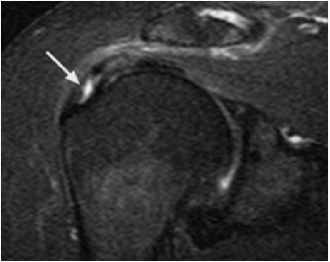

病例:肩袖损伤,男性,50岁,右肩部疼痛2余月。磁共振肩关节成像清晰显示肩袖(冈上肌肌腱)损伤(箭头)。

以腕关节检查为例,患者可以灵活的摆位将腕关节置于体侧,在患者舒适的同时更能获得高质量的图像。反观60cm孔径,患者不得不将手放置在头顶甚至采用俯卧位的方式,并坚持15分钟!这实在是令人难以忍受。